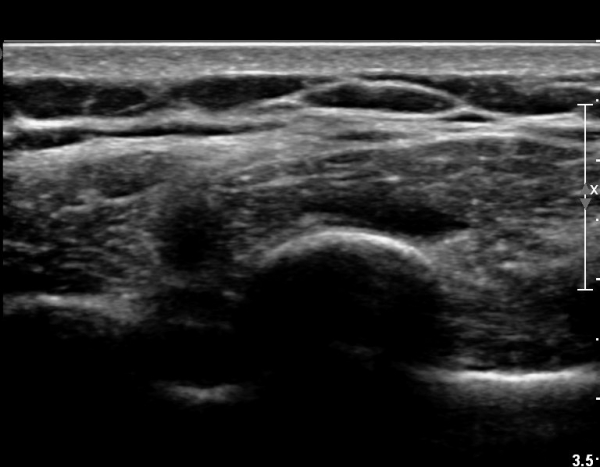

8¹øÂ° °¥ºñ»À Á¾´Ü¸é°Ë»ç»ó °¥ºñ»À Ç¥ÃþÀ¸·Î Àú¿¡ÄÚ ºÎÁ¾°ú °¥ºñ»À Ç¥Ãþ¿¡ ÀÖ´Â

±Ù¼¶À¯µéÀÌ Ç¥ÃþÀ¸·Î ¹Ð·ÁÀÖ´Â °ÍÀÌ °üÂûµÇ°í(»çÁø 1, 2)  °¥ºñ»À ÇÇÁú°ñ ¿¬¼Ó¼º

´ÜÀýÀÌ ÀǽɵȴÙ(»çÁø 2).

8¹øÂ° °¥ºñ»À ¾ÕÂÊ  Á¾´Ü¸é°Ë»ç»ó  Æ¯ÀÌ ¼Ò°ßÀ» º¸ÀÌÁö ¾ÊÀ¸¸¶(»çÁø 4)

ŽÃËÀÚ¸¦ µÚÂÊÀ¸·Î À̵¿ ÇÏ´Ï °¥ºñ»À Ç¥ÃþÀ¸·Î Àú¿¡ÄÚ ºÎÁ¾ÀÌ °üÂûµÈ´Ù(»çÁø 3).